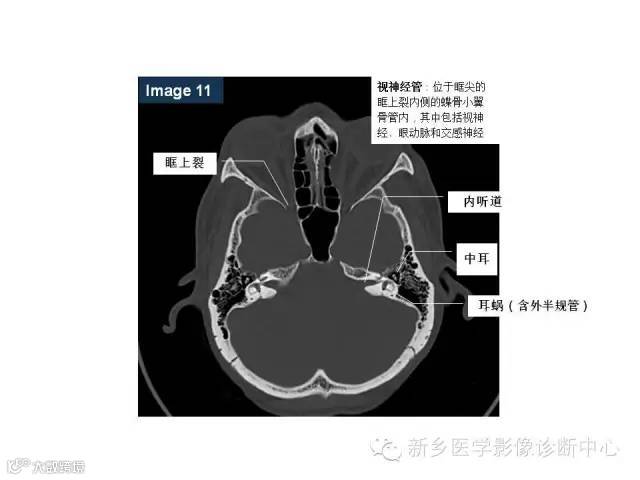

颅底孔道解剖详解

值得收藏!